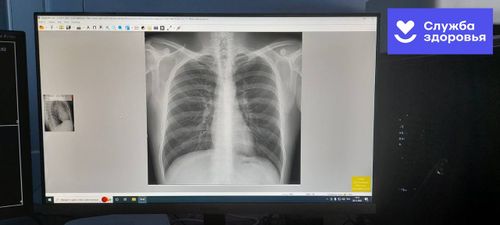

Күзелдиг кижи бүрүзүн чалап турар Апрель 4 болгаш 6 хүннеринде Кызыл хоорайга шимчеп чоруур флюорография аппарады ажылдаар. 04 апреля Кадыкшыл

Баш удур илередири чугула. МАРТ 24 – БҮГҮ-ДЕЛЕГЕЙНИҢ ӨКПЕ ААРЫЫНГА УДУР ДЕМИСЕЛ ХҮНҮ 25 марта Кадыкшыл

Өкпе аарыын соксадыылы Бай-Тайга кожуунга Бүгү-делегейниң өкпе аарыынга удур демисел хүнүнге тураскаадып акцияны эрттирген. 25 марта Кадыкшыл

Чидиг айтырыг болуп артпышаан МАРТ 24 – БҮГҮ ДЕЛЕГЕЙДЕ ТУБЕРКУЛЁЗКА УДУР ДЕМИСЕЛ ХҮНҮ 24 марта Кадыкшыл